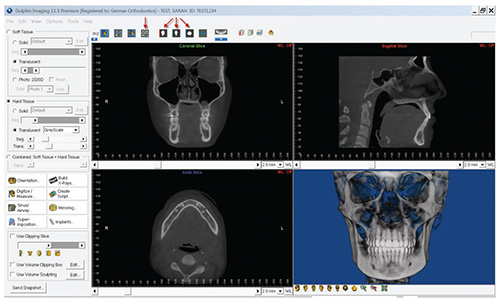

required by an experienced technician to build the images for

our template (the German template) in Dolphin Imaging is

approximately six minutes (Fig. 2).

The German template of images is intended to ensure that a

comprehensive evaluation of the data occurs for every patient,

and that the appropriate data is shared with colleagues. Each

new patient scan is scrutinized as articulated in the publication,

viewing all data in three multiplanar views (sagittal, axial and

coronal), followed by an additional review of the images created

in the German template. A very basic explanation of the purpose

of each of the views and the information gleaned from them is

described in the JCO publication.4